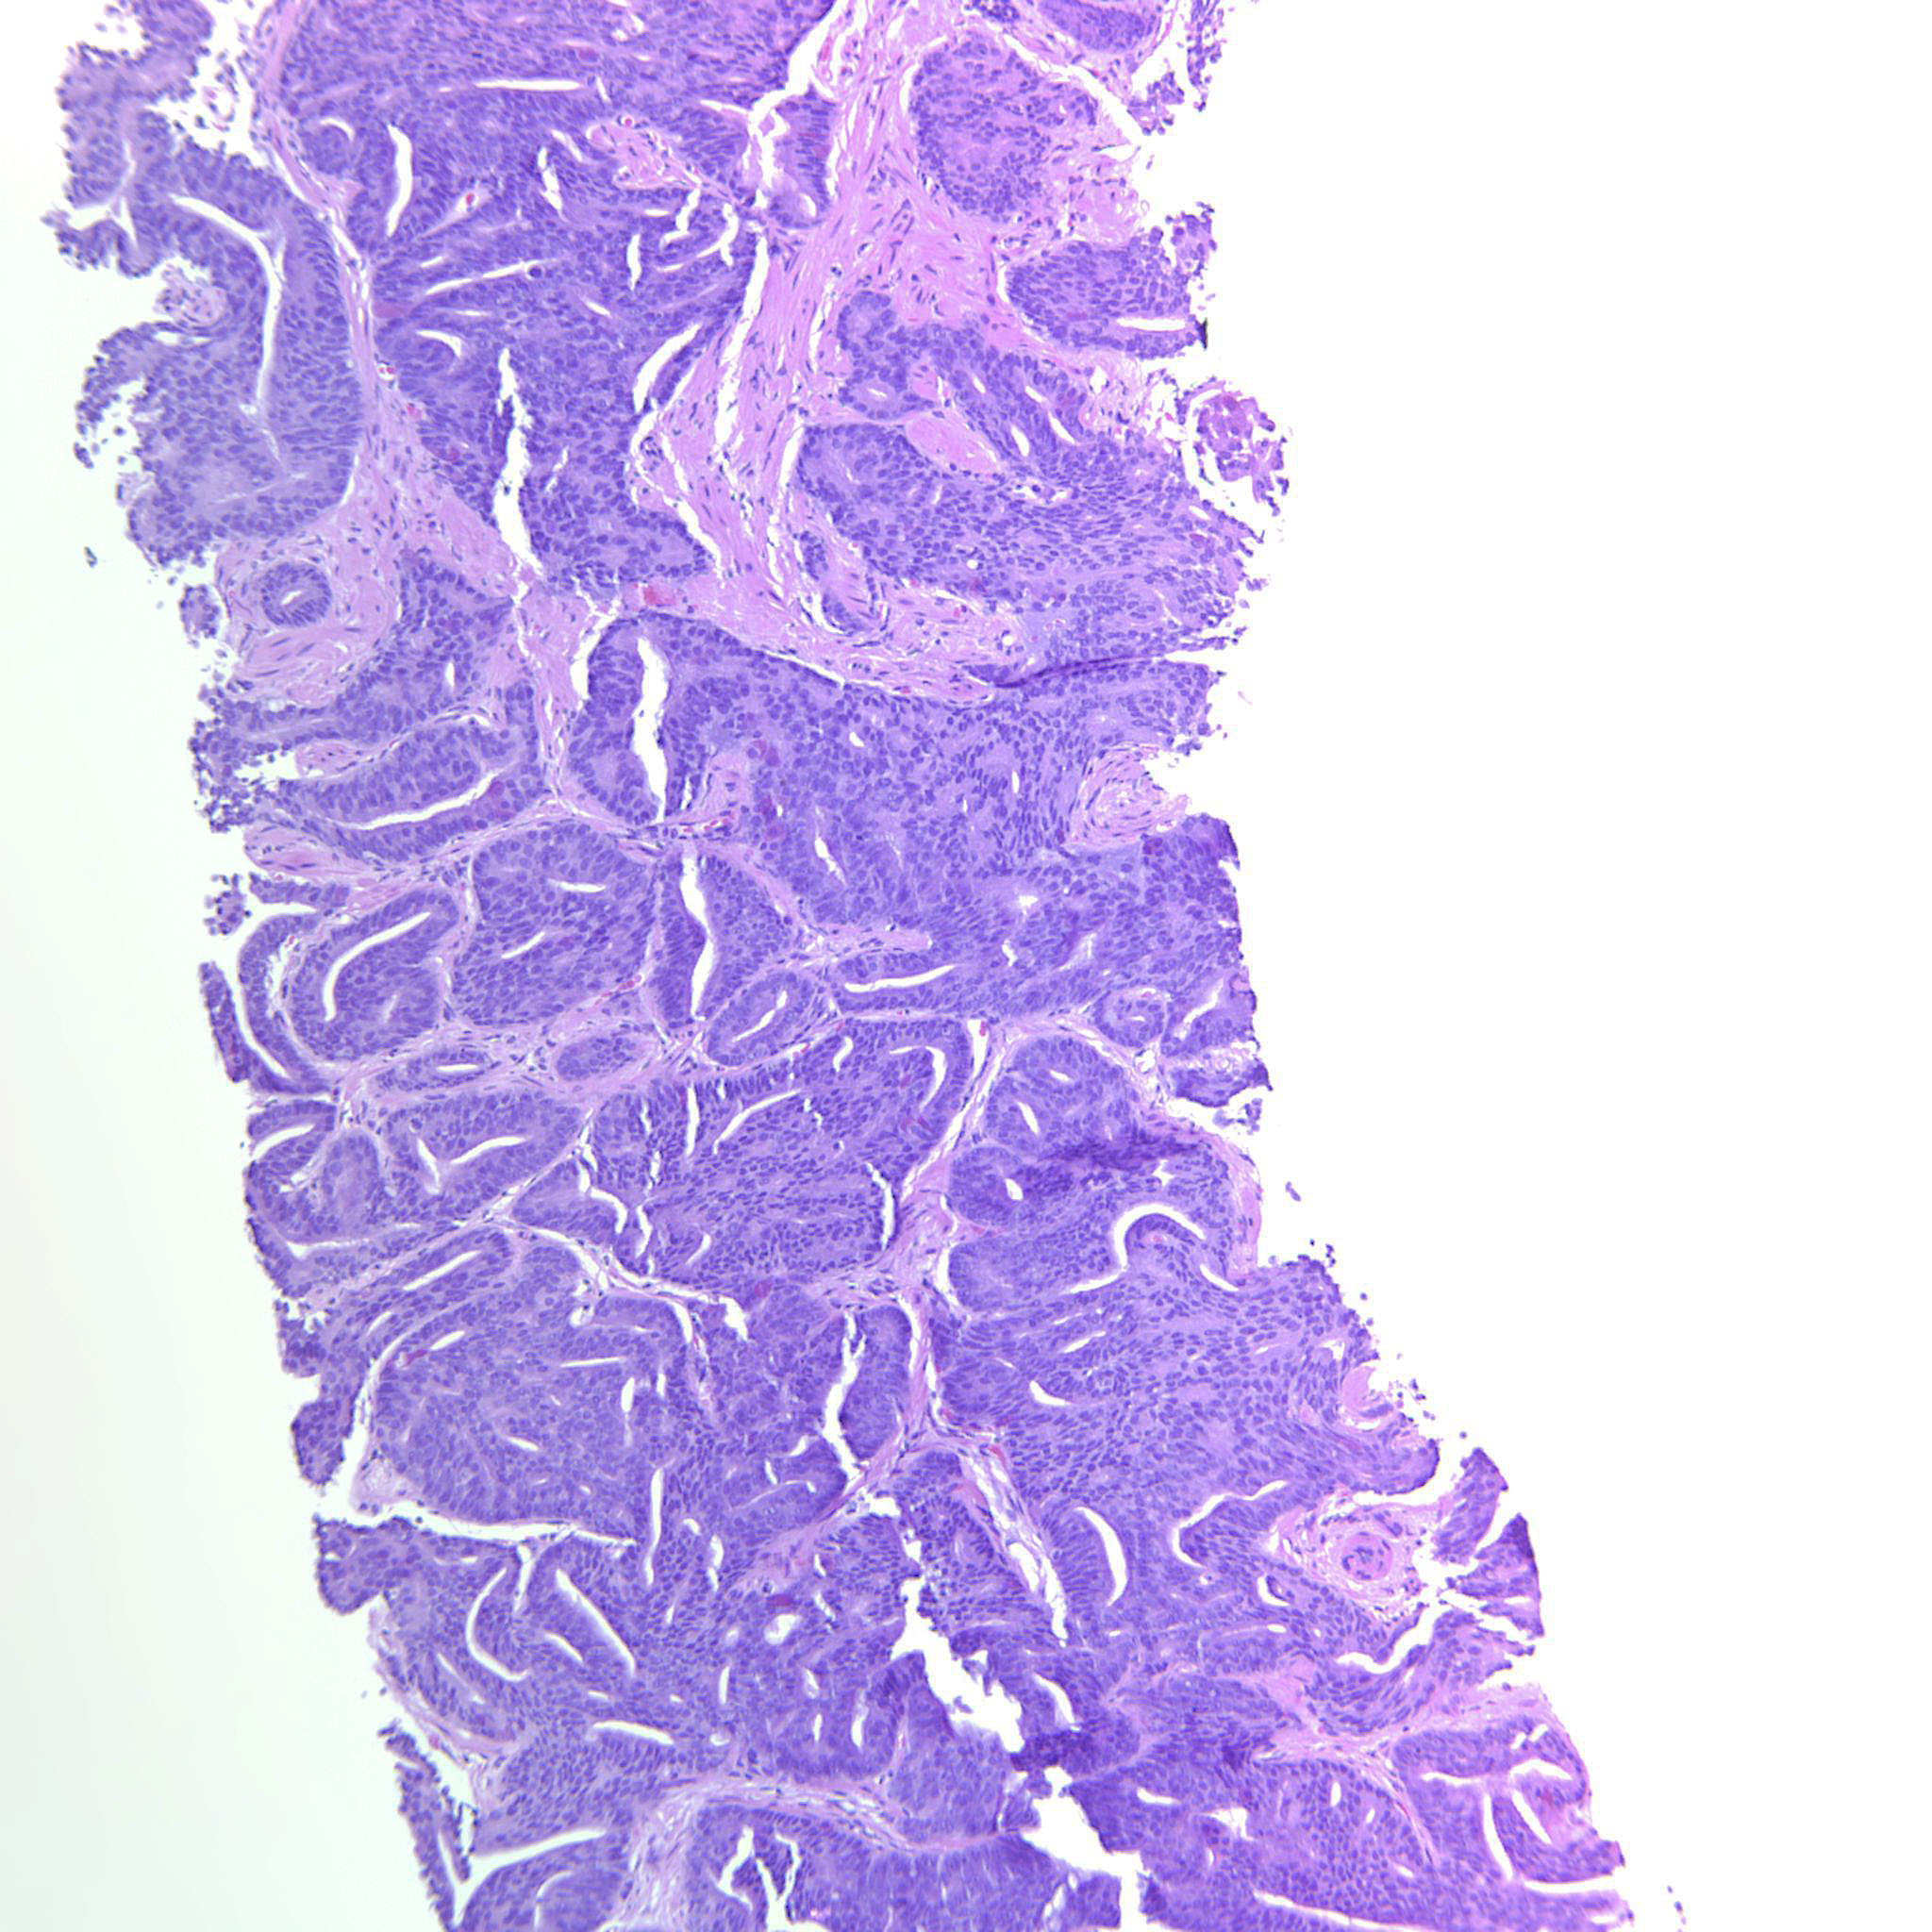

Case description (by case creator):

Areas with cribriform GP4 and other areas with poorly formed glands mixed with well-formed glands. There are also some seemingly solid strips of epithelium but these may possibly be tangential cuts.